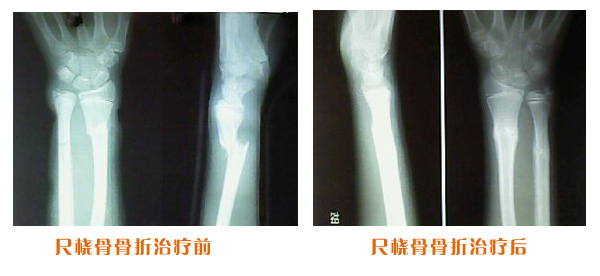

肥城市安駕莊梁氏骨科醫(yī)院是一所以梁氏手法正骨配合膏藥為特色的現(xiàn)代化??漆t(yī)院。

梁氏骨科術(shù)始創(chuàng)于清雍正年間,歷經(jīng)八代,至今已有三百年歷史。據(jù)1929年泰安縣志載“梁瑞圖先生,字增生,號蓮峰,安駕莊人,精岐黃并發(fā)明接骨,凡跌打車凡跌打車軋皮不破而碎骨者......【詳細】 |